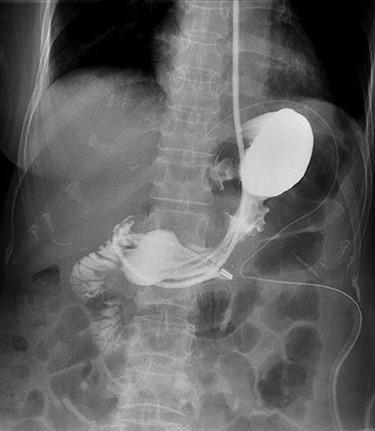

Operative time was 200 min. Postoperatively, she was kept on sips of water until postoperative day (POD) 5 which she had water-soluble contrast study that showed no anastomotic leak (Fig. 5). Feeds and diet were escalated accordingly, and she was discharged on POD 7. She was reviewed in outpatient clinics 3 weeks upon discharge and had no dysphagia or reflux symptoms. The histopathology report was GIST, of high mitotic rate and margins were clear.